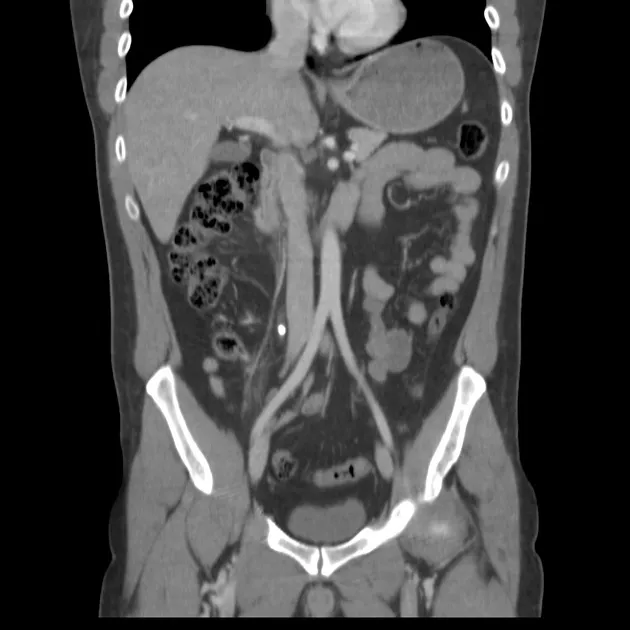

A 45-year-old woman presents with dysuria, frequency, and suprapubic pain. Dipstick shows nitrites positive and leucocytes 3+. This straightforward presentation of contrasts sharply with the diagnostic challenge of unexplained AKI, where systematic investigation must distinguish between pre-renal, intrinsic, and post-renal causes. The diagnostic sequence begins with bedside tests (urine output monitoring, dipstick), progresses through blood tests (creatinine, urea, electrolytes, venous gas), and culminates in imaging when obstruction is suspected. For , non-contrast CT KUB has 95-98% sensitivity for stones >3 mm, far exceeding ultrasound (45% sensitivity). require interpretation in clinical context: a sodium of 128 mmol/L may be asymptomatic chronic hyponatraemia or acute symptomatic requiring urgent correction.

| USS (hydronephrosis) | 90% | 95% | First-line for suspected obstruction |

| Renal colic | CT stone + hydronephrosis | Analgesia, antiemetic, α-blocker | Stone passage or intervention |